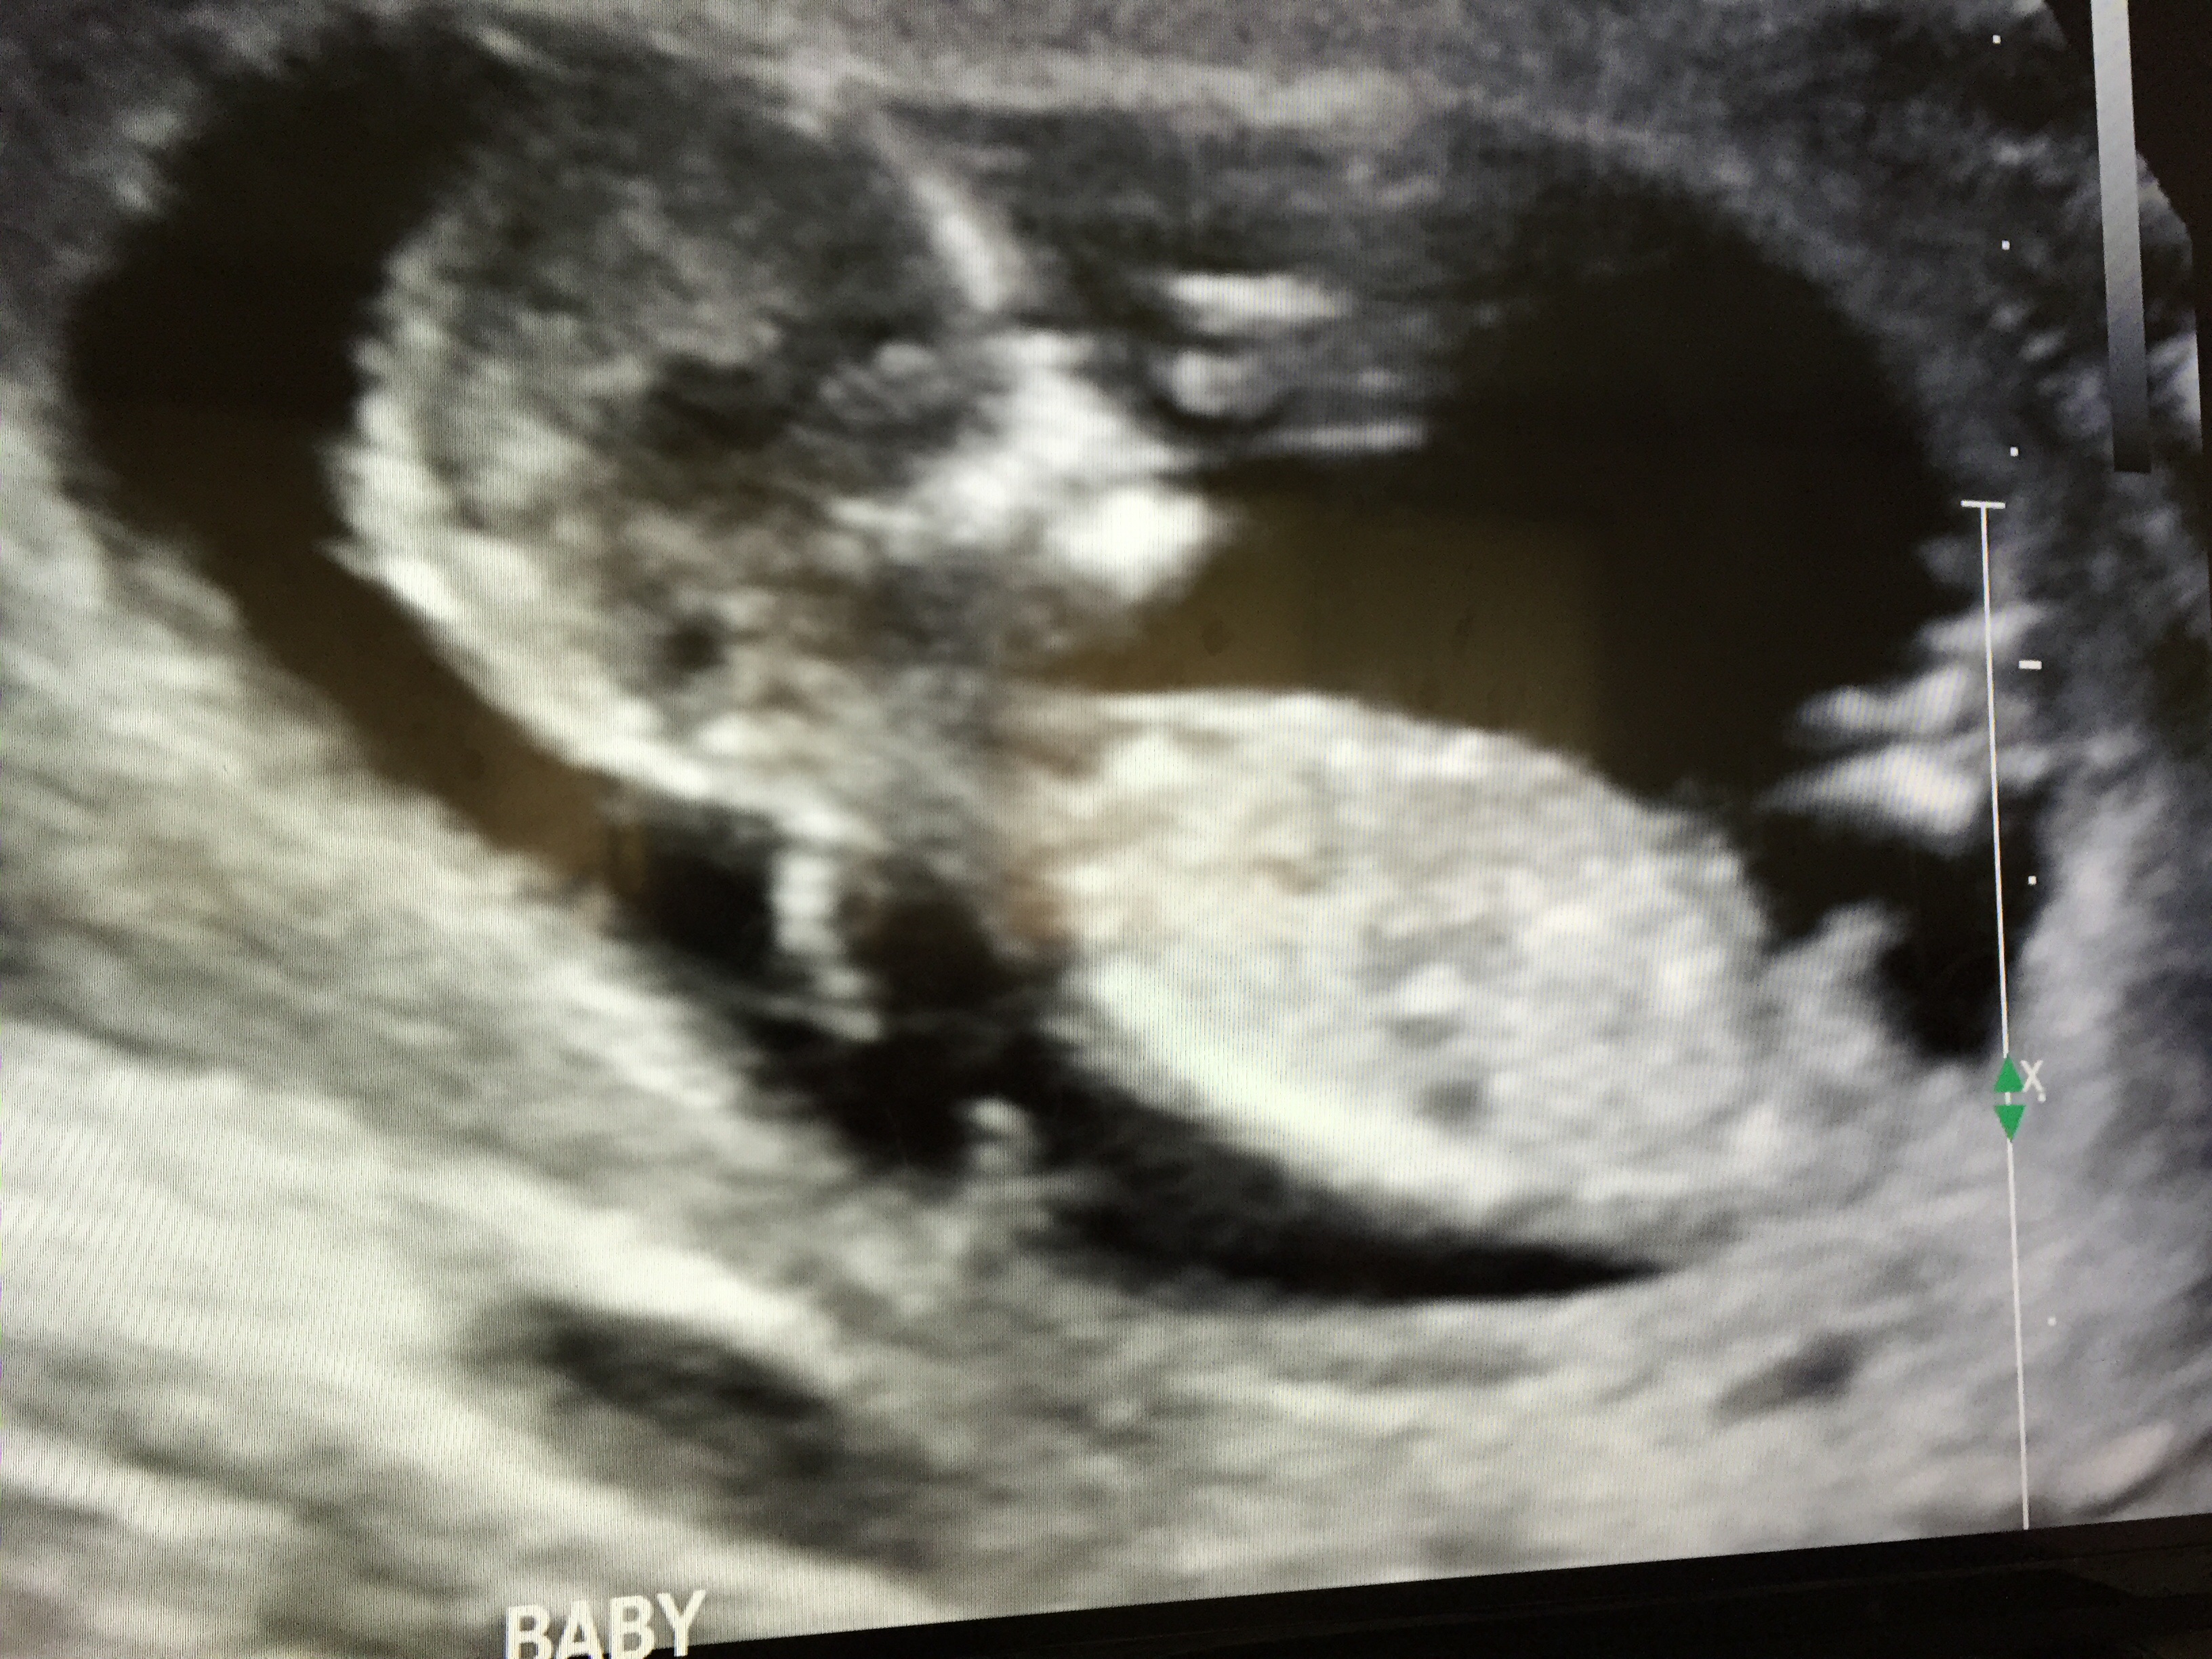

Attachment 25228

I don't know if this is any better. I'm new to the nub theory. When I can look at my disk on a computer I'll see if there is a better one

Boy! What are you hoping for?

Would be very very nice to have a boy since we have a 2 year old girl but of course we'll be happy with either :)

Oh yes, that last pic is all boy!!

Little man